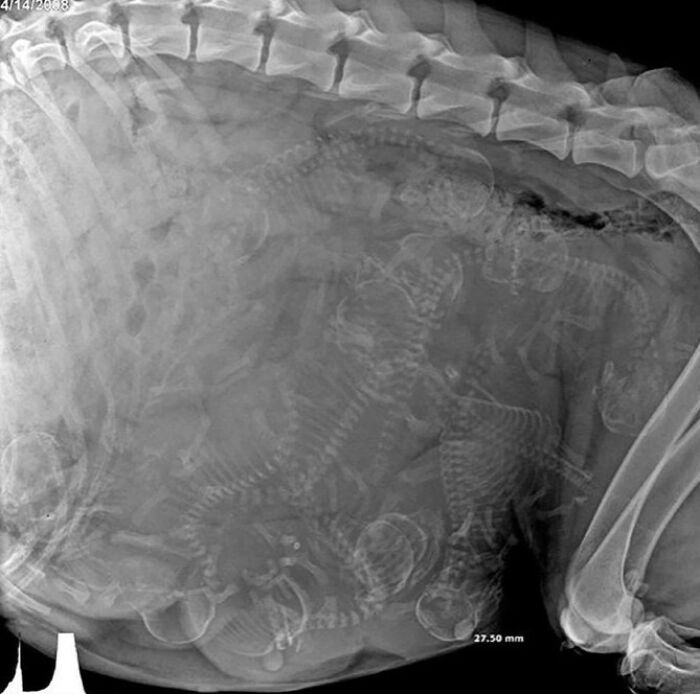

X-Ray Image Showing The Pregnancy Of A Dog